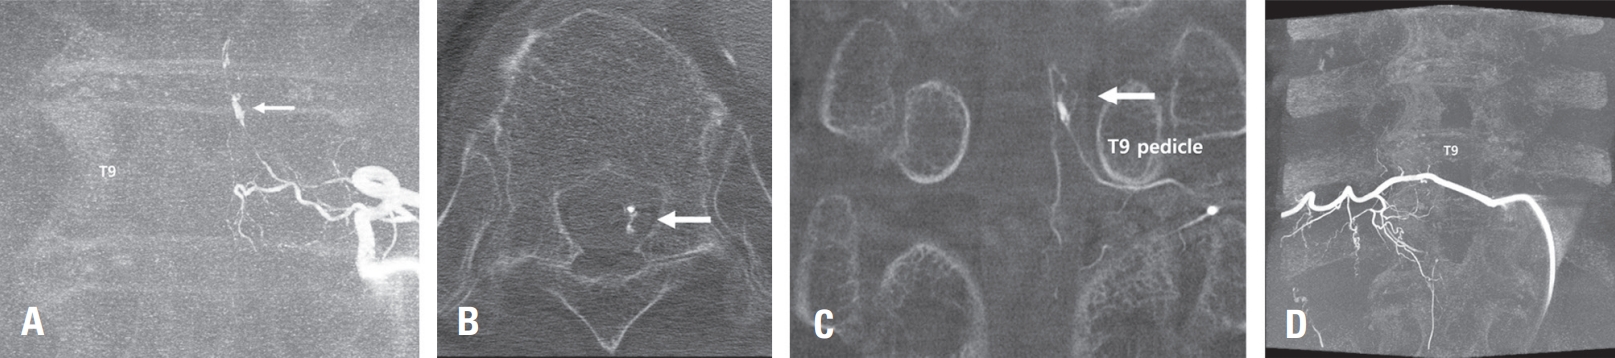

A 75-year-old female patient presented with sudden onset back pain and paraplegia of both lower extremities. Upon admission, her mental status was alert, and she complained of severe back pain. Due to the intensity of her symptoms, a contrast-enhanced MRI of the thoracic spine was immediately performed. The MRI finding

revealed a subdural hematoma extending from the C6 to T11 level, with evidence of spinal cord compression. On the contrast-enhanced images, a heterogeneously enhancing mass was observed at the T9 level of the thoracic spine (Fig 3A, B). Further spinal angiographic examination revealed a aneurysm originating from the right T10 radicular artery (Fig 3C, D, E). As a catheter could be advanced into the parent artery and considering the severe neurological deficit, an immediate embolization procedure was decided upon. The catheter was positioned in the proximal intercostal artery at the T10 level, and the aneurysm was occluded using a combination of glue and coils at the proximal radiculopial artery (Fig 3F). Three weeks after the procedure, a follow-up MRI scan showed resorption of the subdural hematoma; however, the paraplegia demonstrated no neurological improvement (Fig 3G, H).

Fig. 3.

Initial T2 weighted MRI showing a large amount of subdural hematoma extending from C6 to T11, along with evidence of spinal cord edema due to neural compression (A, B). Spinal angiogram image showing a saccular aneurysm in the right T10 radiculopial artery, which was identified as the ruptured aneurysm (C, arrow). CT reconstruction image of spinal angiogram showing the anatomical position of spinal aneurysm (D, E). Intraoperative angiogram image showing catheter position and embolization materials (coil and glue) used to occlude the aneurysm (F). Follow-up MRI at three weeks post-procedure demonstrating resorption of subdural hematoma and persistent T2 hyperintensity in the spinal cord at T9/10 level, suggestive of sequelae of compressive myelopathy (G, H).

Fig. 3. Initial T2 weighted MRI showing a large amount of subdural hematoma extending from C6 to T11, along with evidence of spinal cord edema due to neural compression (A, B). Spinal angiogram image showing a saccular aneurysm in the right T10 radiculopial artery, which was identified as the ruptured aneurysm (C, arrow). CT reconstruction image of spinal angiogram showing the anatomical position of spinal aneurysm (D, E). Intraoperative angiogram image showing catheter position and embolization materials (coil and glue) used to occlude the aneurysm (F). Follow-up MRI at three weeks post-procedure demonstrating resorption of subdural hematoma and persistent T2 hyperintensity in the spinal cord at T9/10 level, suggestive of sequelae of compressive myelopathy (G, H).